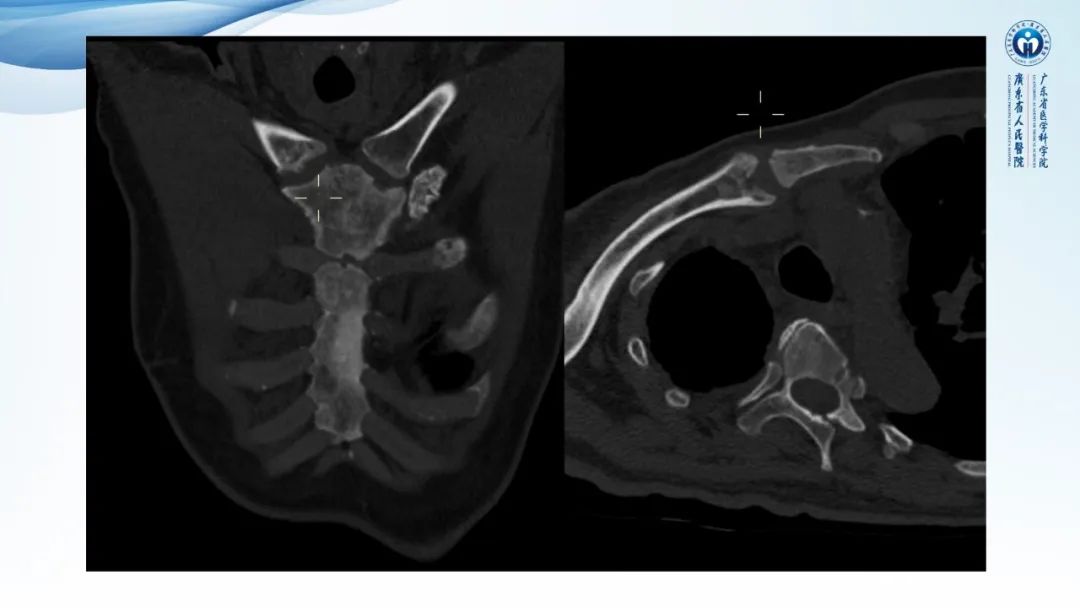

【病例】一例表现为弥漫中轴骨骨质增生硬化病变讨论-2